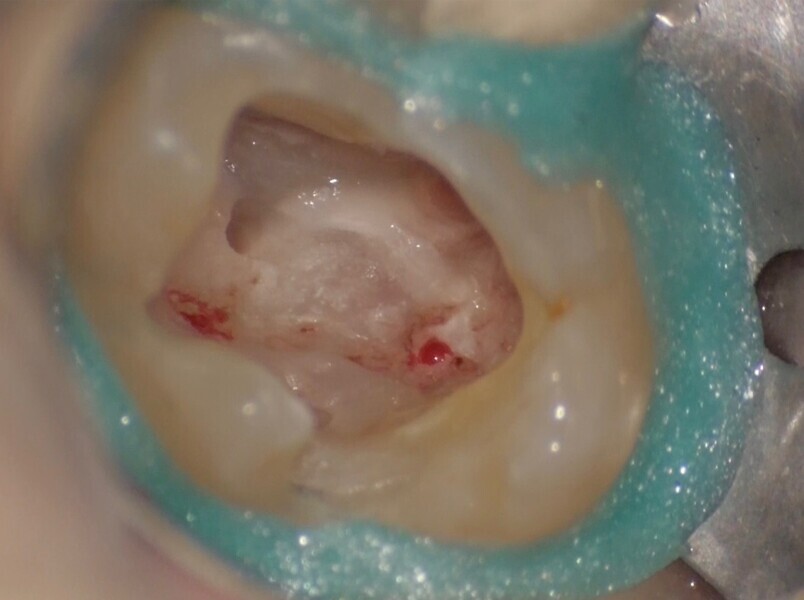

Use of 3D technology in the diagnosis and treatment of endodontic disease